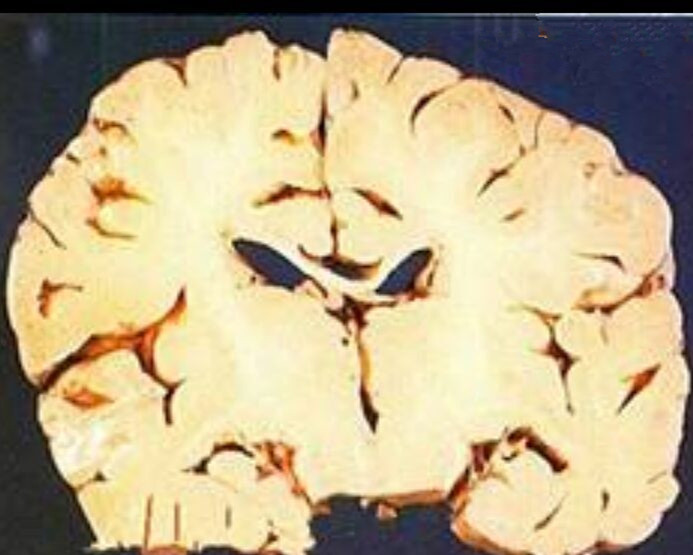

細菌性腦膜炎的解剖

細菌性腦膜炎的腦

腦膜炎細菌性腦部

腦膜炎細菌性